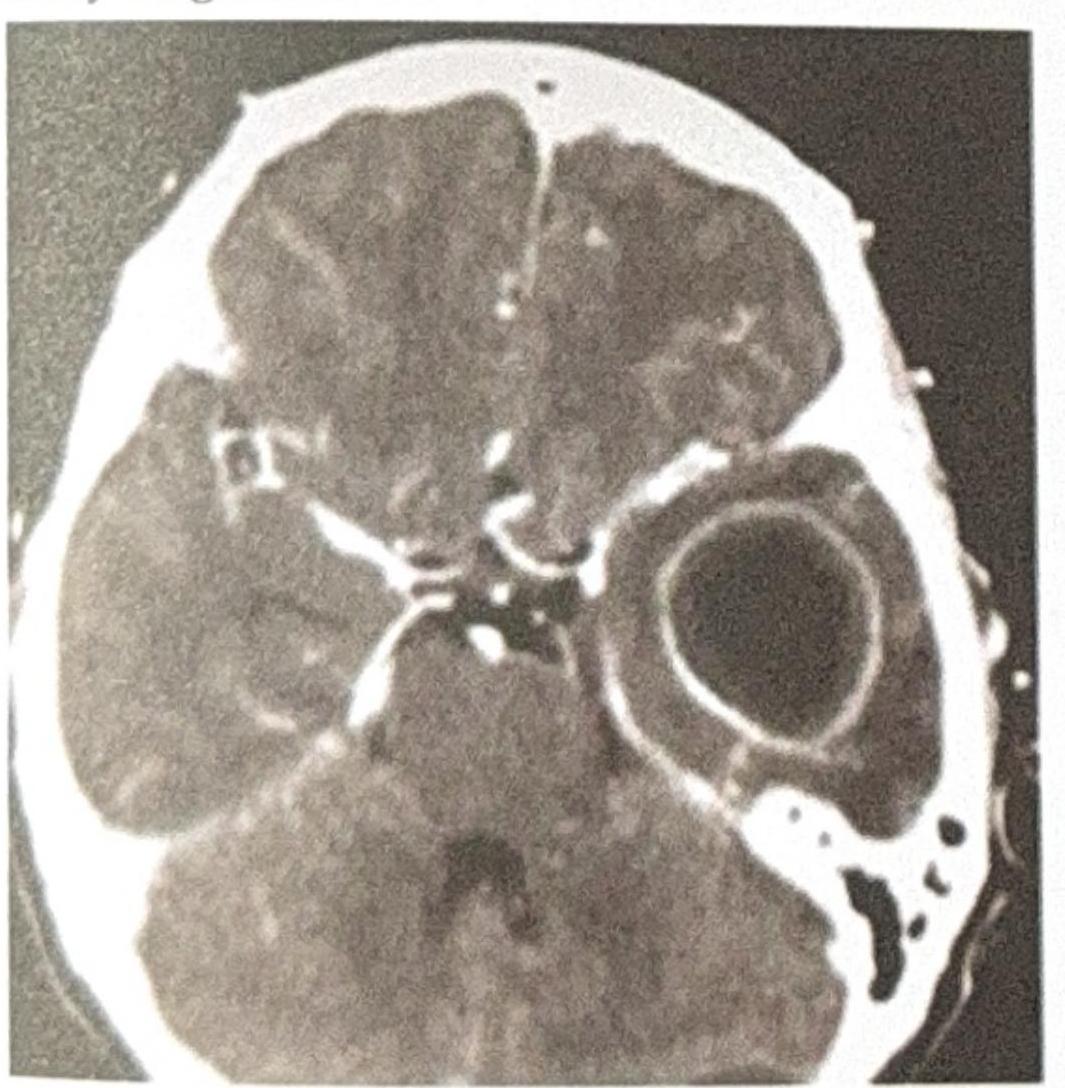

A patient presents with ear discharge. The CT image is shown below. Based on the clinical presentation and imaging, what is the most likely diagnosis?

A patient with a history of chronic ear infection now presents with manifestations, including headache and vomiting. A CT brain image is shown. What is the most probable diagnosis?

Explanation: ***Temporal lobe abscess*** - The CT scan shows a **ring-enhancing lesion** in the **temporal lobe**, which is characteristic of a brain abscess. - **Ear discharge** (otorrhea), particularly from otitis media, is a common predisposing factor for temporal lobe abscesses due to the proximity of the middle ear and mastoid to the temporal lobe. - Otogenic brain abscesses account for a significant proportion of intracranial complications from ear infections, with the temporal lobe being the most common location. *Extradural abscess* - An **extradural abscess** would typically be located between the dura mater and the skull, often presenting as a **lenticular or biconvex collection** displacing the dura and brain, not within the brain parenchyma as seen here. - While ear infections can lead to extradural abscesses, the imaging clearly shows an intraparenchymal lesion. *Cerebellar abscess* - A **cerebellar abscess** would be located in the cerebellum (posterior fossa), which is a different anatomical location from the lesion seen in the image (which is in the supratentorial compartment, consistent with the temporal lobe). - Although ear infections can also lead to cerebellar abscesses, the lesion's position on the CT scan does not correspond to the cerebellum. *Meningitis* - **Meningitis** is an inflammation of the meninges and typically manifests on CT as **leptomeningeal enhancement**, particularly in the sulci and basal cisterns, rather than a discrete, encapsulated mass lesion like an abscess. - While ear discharge can be associated with meningitis, the imaging findings strongly point to an abscess, not diffuse meningeal inflammation.

Explanation: ***Temporal lobe Abscess*** - The CT scan shows a **ring-enhancing lesion** with significant surrounding edema, which is characteristic of a **brain abscess**. - Given the history of a **chronic ear infection**, the temporal lobe is a common site for bacterial spread from the mastoid air cells or middle ear. *Meningitis* - Meningitis involves inflammation of the **meninges** and typically presents with diffuse changes on imaging, such as sulcal effacement or leptomeningeal enhancement, rather than a focal, encapsulated lesion. - While it can cause headache and vomiting, the CT image does not show findings typical of meningitis. *Extradural Abscess* - An extradural (or epidural) abscess is located **between the dura mater and the skull bone**. - It would typically appear as a collection outside the brain parenchyma, potentially causing mass effect but distinct from an intraparenchymal lesion seen in the image. *Cerebral Abscess* - The image does show a **cerebral abscess**, but this option is less specific than "Temporal lobe abscess." - The question asks for the **most probable diagnosis**, and combining the imaging findings with the patient's history of ear infection points to a specific location within the cerebrum.